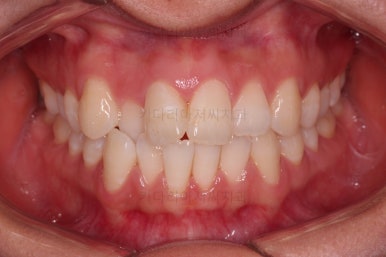

종료 시 사진입니다.

중앙선, 교합, 치아배열 모습 모두 양호해졌습니다.

부산교정잘하는치과 전후 비교해 보겠습니다.

치열도 당연히 좋아졌지만 웃을 때 보이는 치열도 매우 예뻐졌습니다.

입매도 본인이 원하는 수준으로 딱 멈춰드렸고, 적절하게 자연스럽게 약간 들어가고 마무리가 되었습니다.

전반적으로 매우 만족하신 치료가 되었습니다.